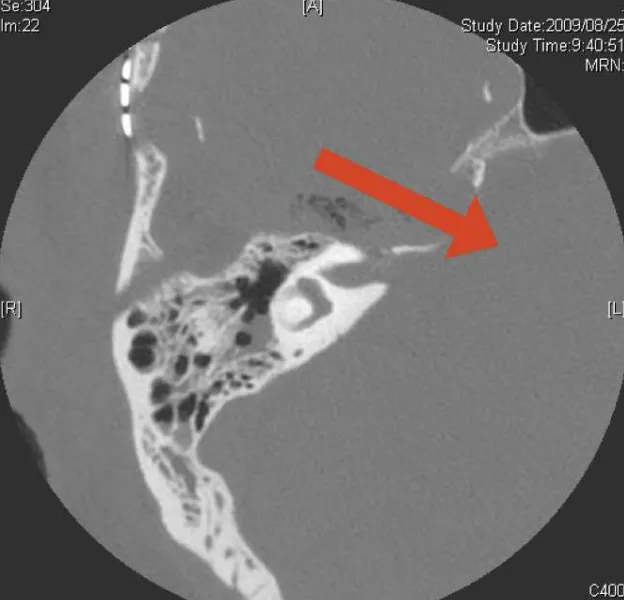

图1. 大型岩斜脑膜瘤术后轴位CT,红色箭头显示从前岩骨切除术后中颅窝通往后颅窝的手术通道

术后轴位视图标注——浅蓝色为钻磨起点与内听道间距(N1),红色为钻磨终点与内听道间距(N2),深蓝色为钻磨起点与最近半规管间距(N3),黄色为轴位最近钻磨边缘到岩尖间距(N4),黑色为轴位钻磨入口长度(N5),白色为轴位钻磨出口长度(N6)